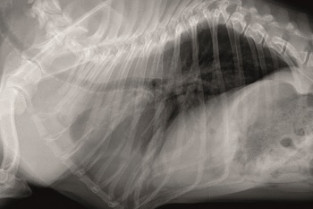

La section Ouest vous propose une soirée d'imagerie thoracique. A l'issue de cette soirée, le participant devra être capable de décrire l'aspect radiographique du mediastin, de l'espace pleural et des poumons. Il devra aussi être capable de localiser et qualifier les principales lésions thoraciques.

• Décrire l'aspect du mediastin de l'espace pleural et des poumons en radiographie

• Localiser et qualifier les principales lésions radiographiques thoraciques